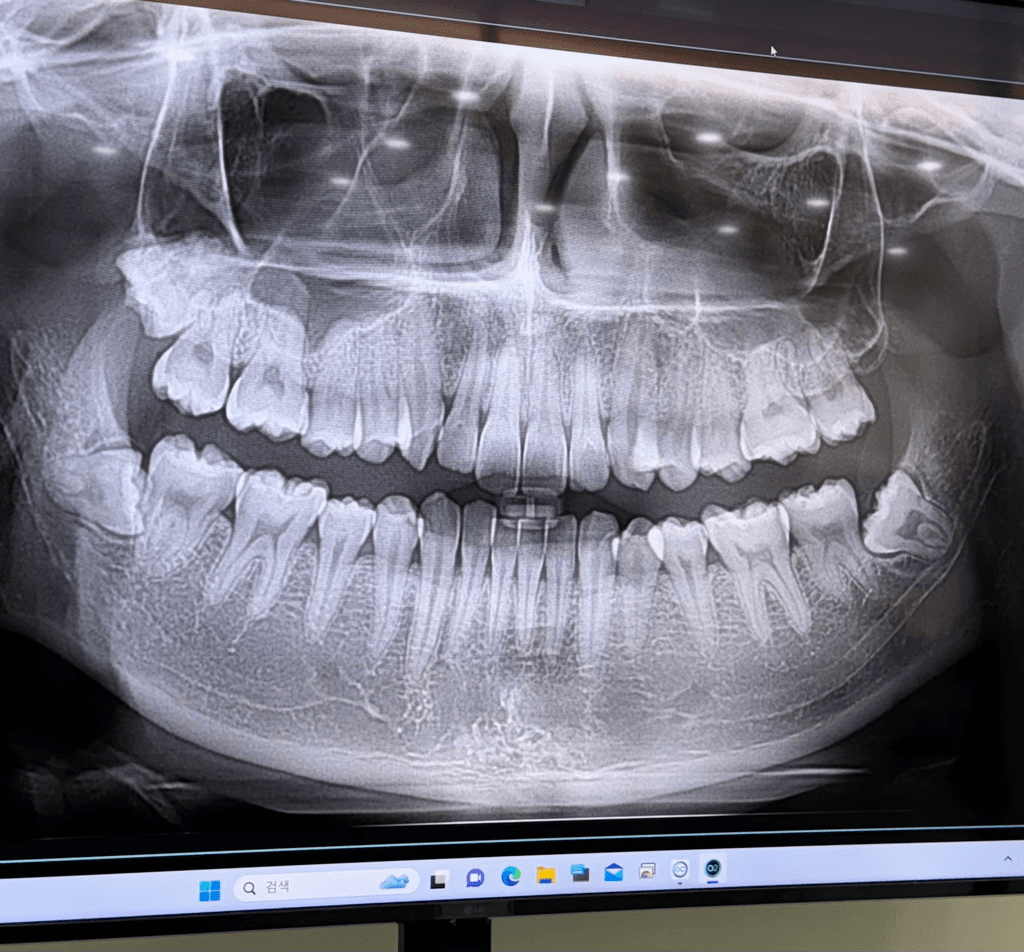

왼쪽 위아래 사랑니가 나야할 자리에 위아래로 연결된 끈 같은게 있는데 한 두달전부터 입벌릴때마다 땡기고 아픕니다. 오른쪽 아래어금니 크라운을 씌울 때 입을 계속 벌리고있었는데 그 때부터 의식하게돼서그런지 자꾸 신경쓰입니다. 사랑니가 나는 자리에도 약간 꺼끌꺼끌하게 상처같은게 나있는 것 같아요(혀로 만지면 느껴집니다.) 입을 최대한 크게 벌리면 저 끈같은게 끊어질 듯 아프고 사진도 자세히 보시면 말씀드린 끈같은것에 노란색 고른같은게 있어보입니다. 구강암같은 것일까요...? 치과에서는 별 말씀 없으셨었습니다.

1. 해당 구조는 pterygomandibular raphe라고 하며 정상 구조물입니다.

2. 오른쪽 위,아래로는 사랑니가 있고 왼쪽의 경우 아래는 사랑니가 있습니다.

3. 노란색은 구강 내 지방조직 내지는 염증으로 추측됩니다.